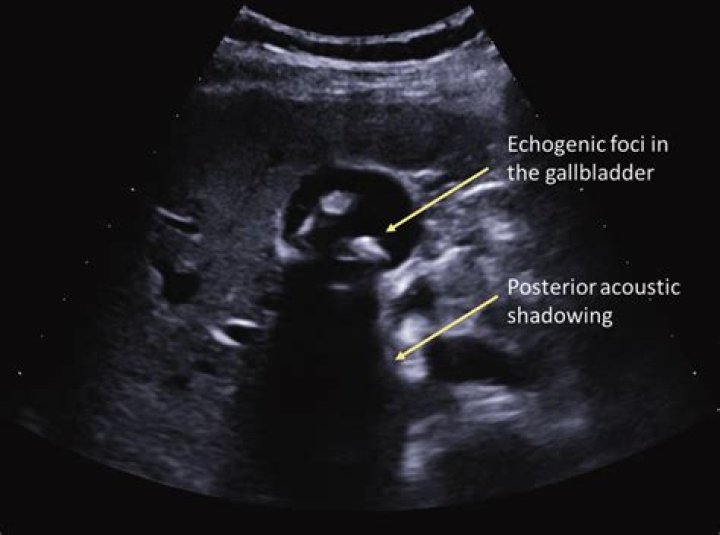

Gallstones on ultrasound have the appearance of hyperechoic structures within the gallbladder with distal acoustic shadowing. Sludge in gallbladder may also be seen, with an appearance of hyperechoic layering within the gallbladder. Sludge, unlike stones, does not cast acoustic shadowing.

Gallstones appear as echogenic foci in the gallbladder. They move freely with positional changes and cast an acoustic shadow. (See the image below.) Cholecystitis with small stones in the gallbladder neck.

What are shadowing gallstones?

Air present within gallbladder calculi creates reverberation artifacts and a dirty shadow. Small stones produce an acoustic shadow only if scanned by a high-frequency transducer (5 MHz or higher), since these transducers have a smaller beam width. A shadow is produced only if the stone intercepts the entire beam.